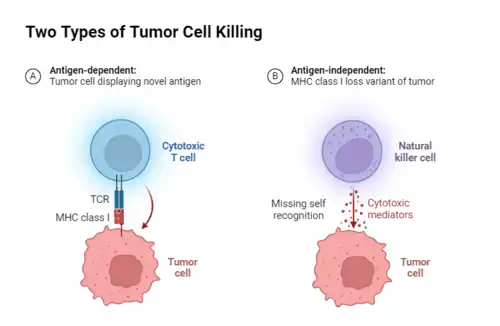

De maneira geral, a evasão imunológica, mecanismos pelos quais células cancerosas conseguem evitar ser reconhecidas e destruídas pelo sistema imunológico do corpo, pode ser vista como um resultado da seleção natural dentro do ambiente tumoral. As células cancerosas apresentam mutações, alta diversidade genética e antigênica e capacidade de expressar moléculas de superfície semelhantes às células normais ou a proteínas do próprio sistema imunológico e secretar fatores imunossupressores que limitam a atividade de células imunes pró-inflamatórias e promovem a expansão de células supressoras. Estas características, junto ao microambiente tumoral, permite a evolução de variantes ou condições que suprimem ou modulam a atividade do sistema imunológico, impedindo o seu reconhecimento pelo sistema imunológico, facilitando assim a evasão.[33]

Atualmente, a imunoedição e expressão de HLA são passos importantes na evolução da evasão imunológica e resistência a medicamentos do câncer. A imunoedição descreve um processo de três etapas no qual a seleção pelo sistema imunológico conduz a evolução do tumor em direção à evasão imunológica. Por meio do reconhecimento das células cancerígenas e montagem de uma resposta contra elas, fase de eliminação, os clones imuno resistentes, se surgissem antes da erradicação do tumor, através de mecanismos como instabilidade genômica ou plasticidade epigenética, poderiam ser suficientes para conduzir um tumor a uma fase de equilíbrio. Esta, a qual a morte imunomediada é proporcional à proliferação de células tumorais, tendo nenhum crescimento líquido do tumor ocorrendo. A morte de clones pode, então, selecionar clones imunes evasivos, levando ao escape e ao crescimento de um tumor imune evasivo.[38]

A perda de expressão de HLA I resulta na incapacidade de infiltração de linfócitos. Com o desenvolvimento da seleção imunológica, o número de células negativas para HLA I no tumor aumentou gradualmente, permitindo que as células formem nódulos cancerígenos através do microambiente imunossupressor, impedindo a entrada de linfócitos. Assim, alguns tumores podem ser insensíveis ao tratamento porque têm expressão ou superexpressão de HLA, o que os ajuda a completar o escape imunológico [39]

Visto o conhecimento de como pode surgir um novo tumor a partir da evolução clonal, estudos atuais buscam aplicar essas ideias no combate à doença. Antigamente os médicos tratavam seus pacientes com a maior dose de quimioterapia possível, visando eliminar o tumor antes do surgimento de uma resistência ao tratamento, porém isso só acelerava o processo de dominação das populações de células resistentes a drogas do tumor, sem contar os próprios efeitos colaterais da quimioterapia. Hoje, novas drogas para combater o câncer vêm sendo desenvolvidas, principalmente as terapias direcionadas. Por exemplo as imunoterapias, tratamento que envolve o fortalecimento do sistema imune do paciente para combater as células cancerosas. Elas podem ser divididas em diversos tipos, com destaque para dois deles nas pesquisas atualmente: a terapia adotiva e os inibidores de checkpoint imune (ICI). A terapia adotiva consiste na retirada de células do sistema imune do paciente para cultivá-las in vitro, aumentando sua letalidade direcionada e logo em seguida inserindo-as novamente no paciente. Esta pode ainda ser classificada em vários tipos dependendo da célula a ser retirada para melhoramento, como TCR-T, CAR-T, natural killer (NK) , etc. Já os checkpoint imune são receptores presentes em células autoimunes humanas que controlam a intensidade de ação do sistema imunológico. Porém, da mesma forma que os tumores desenvolveram a imunoedição, também são capazes de controlar esses checkpoints a seu favor, enviando sinais para diminuir a atividade de células imunológicas. É aí que entram os inibidores, que atuam sobre os checkpoints para permitir um combate contínuo do sistema imune contra as células tumorais.[34]